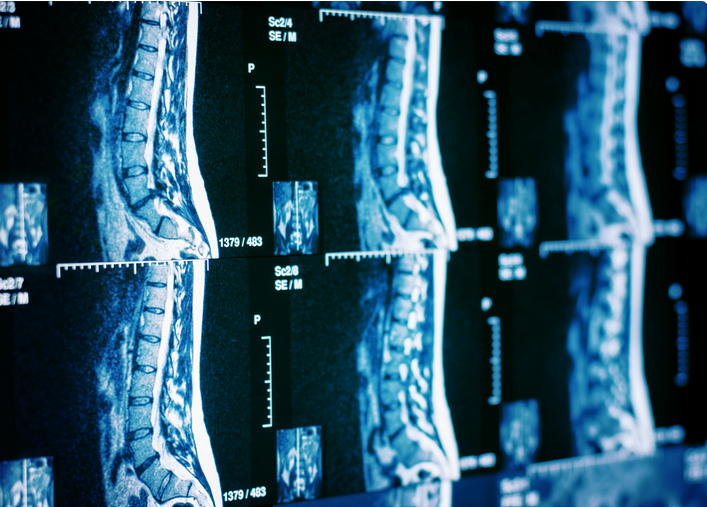

Magnētiskās rezonanse mugurkaula kakla, krūšu, jostas/krustu daļai

MR sniedz daudz vairāk un precīzāku informāciju par smadzeņu anatomiskajām struktūrām – skriemeļiem, starpskriemeļu diskiem, nervu saknītēm, to patoloģiskām pārmaiņām – nekā ierastais rentgena, ultrasonogrāfijas vai datortomogrāfijas izmeklējums. Iespējams diagnosticēt iedzimtas izmaiņas gan skriemeļos, gan muguras smadzenēs, starpskriemeļu disku patoloģiskas pārmaiņas, to ietekmi uz nervu struktūrām, traumatiskas izmaiņas gan skriemeļos, gan muguras smadzenēs, kā arī dažādus veidojumus.